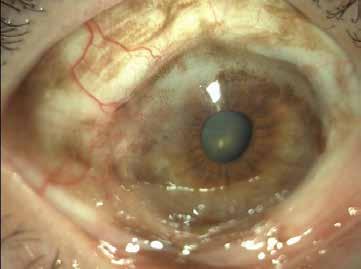

MNV may develop as a complication of chorioretinal inflammation. In this context, MNV may be the first presenting sign of posterior uveitis or may develop in patients with a prior diagnosis.61 MNV can occur in a wide range of uveitis cases, including both infectious and non-infectious etiologies. Distinguishing inflammatory MNV from other forms may be useful due to the implications for managing both the condition and the associated uveitis. The proposed mechanism for the development of inflammatory MNV involves focal disruption of the RPE caused by infection or inflammation, which leads to growth and invasion of new vessels into the outer retinal space.62,63 The most common cause of inflammatory MNV is punctate inner choroidopathy. Other conditions that may be complicated by the development of MNV include multifocal choroiditis, serpiginous choroiditis, presumed ocular histoplasmosis syndrome, toxoplasma retinochoroiditis, and Vogt-Koyanagi-Harada disease.64 In this context, a detailed patient anamnesis and multimodal imaging analysis, including the recently introduced OCTA technology, are highly valuable for diagnosing and managing inflammatory MNV. Central vision loss due to MNV compromises patients’ ability to engage in certain types of work and daily activities. Considering that uveitis often affects individuals of working age, inflammatory MNV frequently impacts patients during their most productive and active years.64 Patients with inflammatory MNV exhibit some differences compared to other conditions such as AMD. In AMD, MNV can present as Type 1, Type 2 or Type 3 lesions, while the inflammatory MNV typically manifests as Type 2 lesions.65,66 In AMD, MNV is usually subfoveal and associated with the presence of drusen, pigmentary changes, and RPE abnormalities, while in inflammatory MNV, the RPE is often intact. Moreover, inflammatory MNV lesions are highly focal and may respond to fewer injections compared to AMD patients, who often require ongoing VEGF suppression with multiple injections.67 In patients with inflammatory MNV, inflammation drives lesion development, and with adequate inflammation control, the neovascular drive may subside. Management of the underlying uveitis typically involves systemic steroids or steroid-sparing immunosuppressive therapy, combined with the MNV management requiring anti-vascular growth factor agents, with or without concurrent anti-inflammatory and/or corticosteroid therapy.